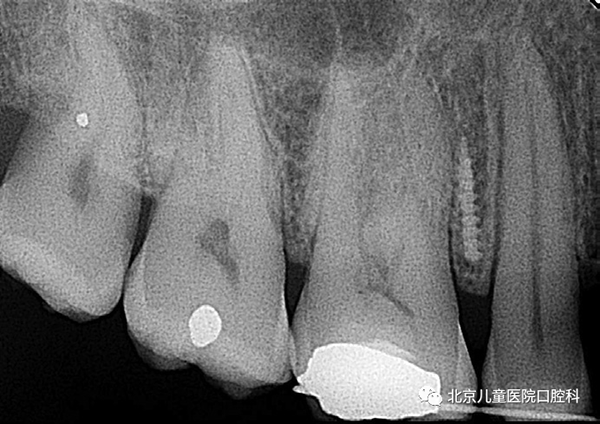

A:1、牙根损伤:较少发生。若植入过程中触碰牙根,医生会重新调整植入的部位和角度。轻微的根触碰,一般在3个月后即可自我修复。